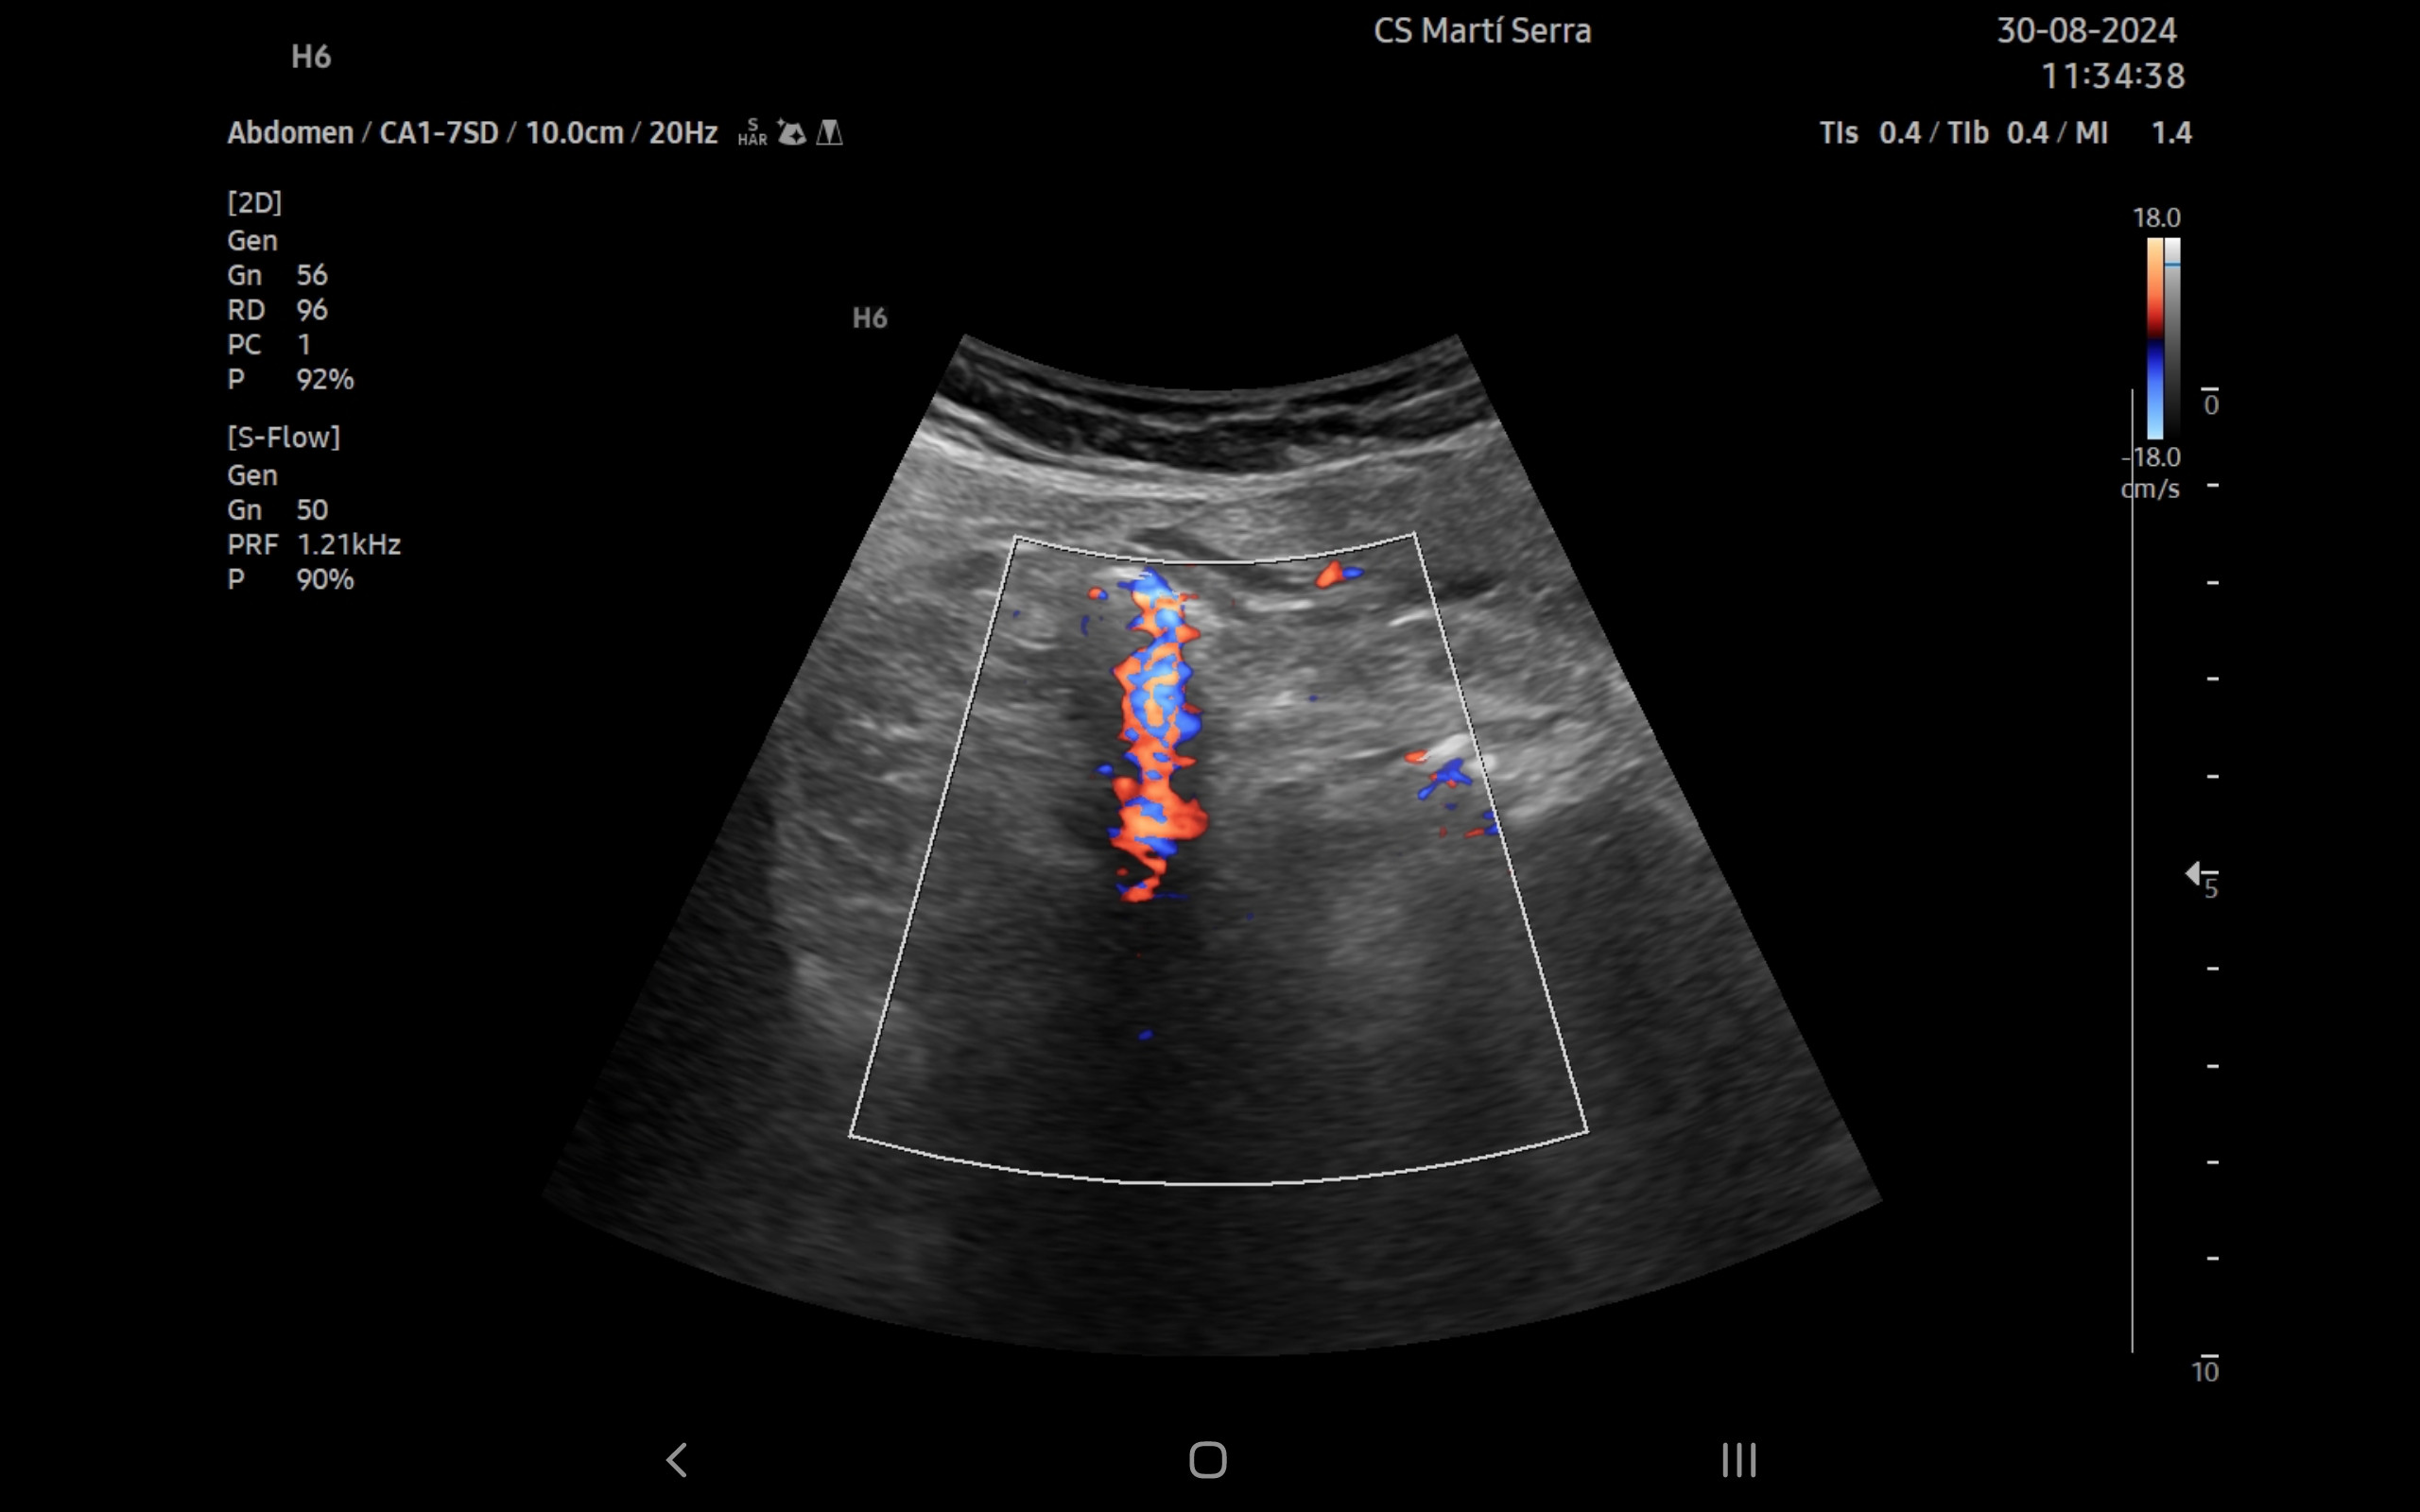

Ecografía clínica:

Imagen hiperecogénica con sombra en interior de vesícula biliar, hígado, páncreas, bazo y riñones sin alteraciones, vejiga orina poco replecionada. Llama la atención mínima imagen anecogénica en fondo de saco de Douglas. Apéndice visible en fid con diámetro 1,07 cm con captación aumentada con apendicolito con fenómeno centelleo.

La ecografía complementa la anamnesis y la exploración física. A día de hoy está disponible en la mayoría de centros de salud. En el caso concreto de la paciente, la discapacidad intelectual limitó la información obtenida de la entrevista. Ante la detección de un apéndice con diámetro mayor de 6 mm, no compresible, captación aumentada y apendicolito, se ha podido diagnosticar el proceso.